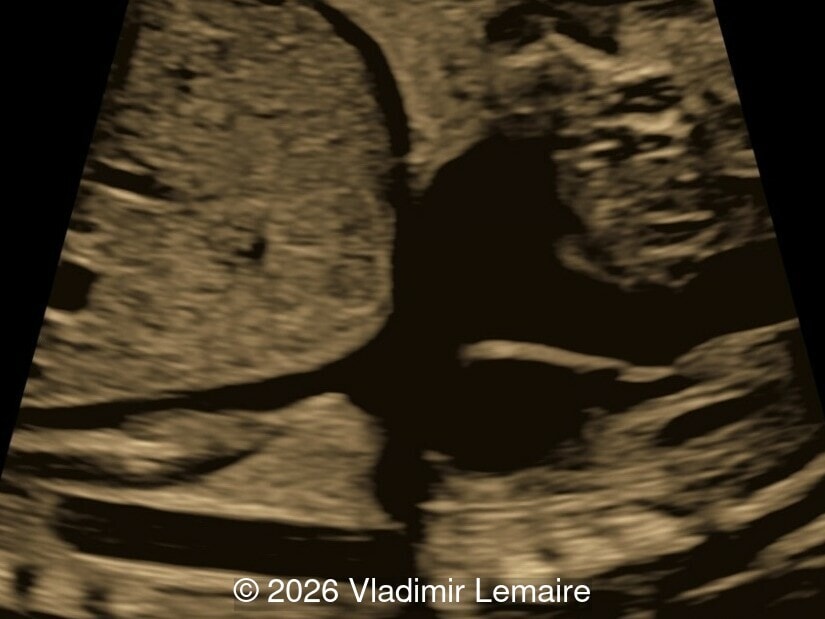

3D glass-body mode at the level of the three-vessel-trachea view. Note the dilation of the superior vena cava.

Image 5 3D glass-body mode at the level of the three-vessel-trachea view. Note the dilation of the superior vena cava.

Our imaging revealed enlargement of the fetal heart with dilation of the superior vena cava. On further evaluation, we identified an elongated anechoic cystic structure in the midline of the head, without mass effect on the surrounding structures. Color doppler demonstrated an arteriovenous fistula between the deep choroidal arteries and the embryonic median prosencephalic vein of Markowski. The vein of Galen aneurysmal malformation was likely the contributing factor to the cardiac enlargement. Cardiac function was, however, preserved and hydrops not present. Additional images are shown below.

On ultrasound, a VGAM appears as an elongated anechoic cystic structure in the middle of the head, often without mass effect on the surrounding structures. Color Doppler shows high-velocity flow in the lesion and can be used to identify the arteries feeding the vascular malformation. Pulsed-wave Doppler shows markedly turbulent flow. Additional key echocardiographic features include an enlarged heart with preserved systolic function, a dilated superior vena cava, and mild or moderate tricuspid regurgitation. Tricuspid regurgitation was not present in our case at the time of our evaluation.